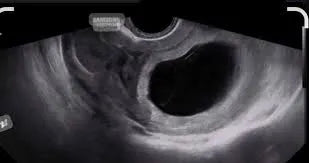

Pourquoi parle-t-on d’œuf clair ? L’échographie donne l’impression d’un œuf vide, car aucun embryon ne s’y trouve. À l’échographie, on observe souvent un sac gestationnel vide sans embryon, ou parfois seulement une vésicule vitelline. Le contenu de l’utérus lors d’un œuf clair se limite donc au sac gestationnel et, dans certains cas, à la vésicule vitelline. Ce diagnostic est généralement posé à un terme situé entre 7 et 13 semaines d’aménorrhée (SA), lors des premières échographies.

1. Échographie de datation (7 SA) : Elle permet de repérer un sac gestationnel vide.

2. Échographie de confirmation : Une semaine plus tard, elle exclut une erreur de datation.

L’échographie endovaginale constitue l’examen de référence pour poser le diagnostic. Celui-ci doit toujours être confirmé par un contrôle à distance afin d’éviter toute erreur liée à une datation imprécise de la grossesse.

Le diagnostic repose avant tout sur l’échographie. Un sac gestationnel mesurant plus de 25 mm sans visualisation d’embryon constitue un critère déterminant. Le suivi sériel des bêta-hCG vient en complément, mais ne remplace jamais l’imagerie dans l’évaluation d’une grossesse non évolutive.